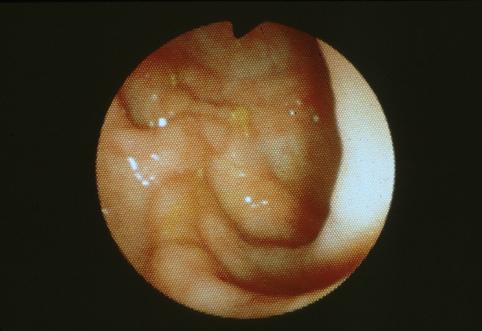

Rectal Crohns disease.

Inflammatory or ulcerative disease / lesions/Crohn disease

Large intestine(Colon)/Rectum

Endoscopy